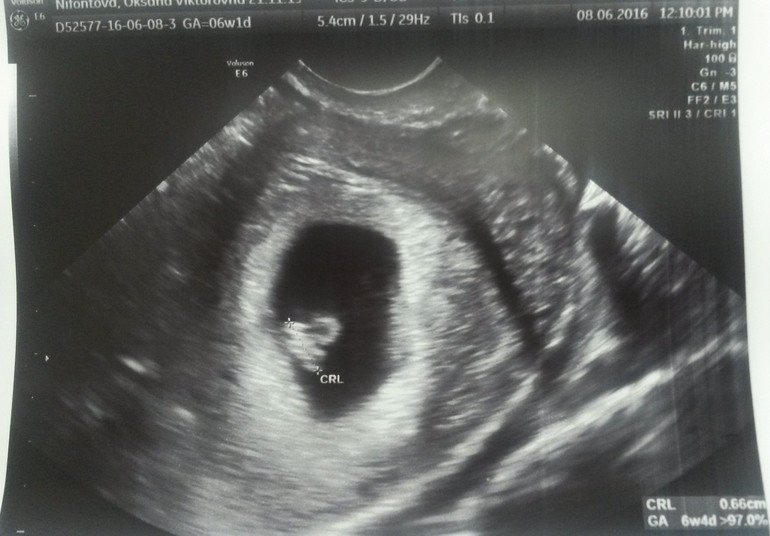

А сегодня с мужем ходили на первое УЗИ, так сказать для подтверждения и успокоения себя) Я так волновалась, что голос мой был тихий, пальцы тряслись, муж обнимал и подбадривал, говорил, что все хорошо! За это ему особое спасибо

Врач УЗИ очень хорошая девушка, все прокомментировала, обо всем рассказала. Я до этого смотрела в интернете фото УЗИ на эти сроки и знала, что я должна увидеть) Вот, значит, датчик и ...вот моя малявочка!

Вроде такие маленькие 0,66 см, но уже есть сердце! И оно бьется!!!

Врач включила звук и мы с мужем услышали ЕГО!!! 154 удара в минуту!

Это не передать словами! Я расчувствовалась! Врач увидела мои слезки и сказала, что плакать нельзя, иначе будет тонус, которого сейчас нет! Все у нас хорошо. По размерам и всем остальным параметрам соответствуем срокам. Крепимся по задней стенке, значит, сказала, живот появиться позже. Мало в это верю почету-то)))